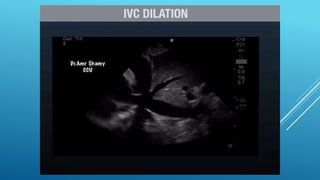

โ€ข RV End diastole diameter > 41 mm (base) and

โ€ข > 35 mm (mid level)=RV dilatation

โ€ข > 83 mm (longitudinal) = RV enlargement